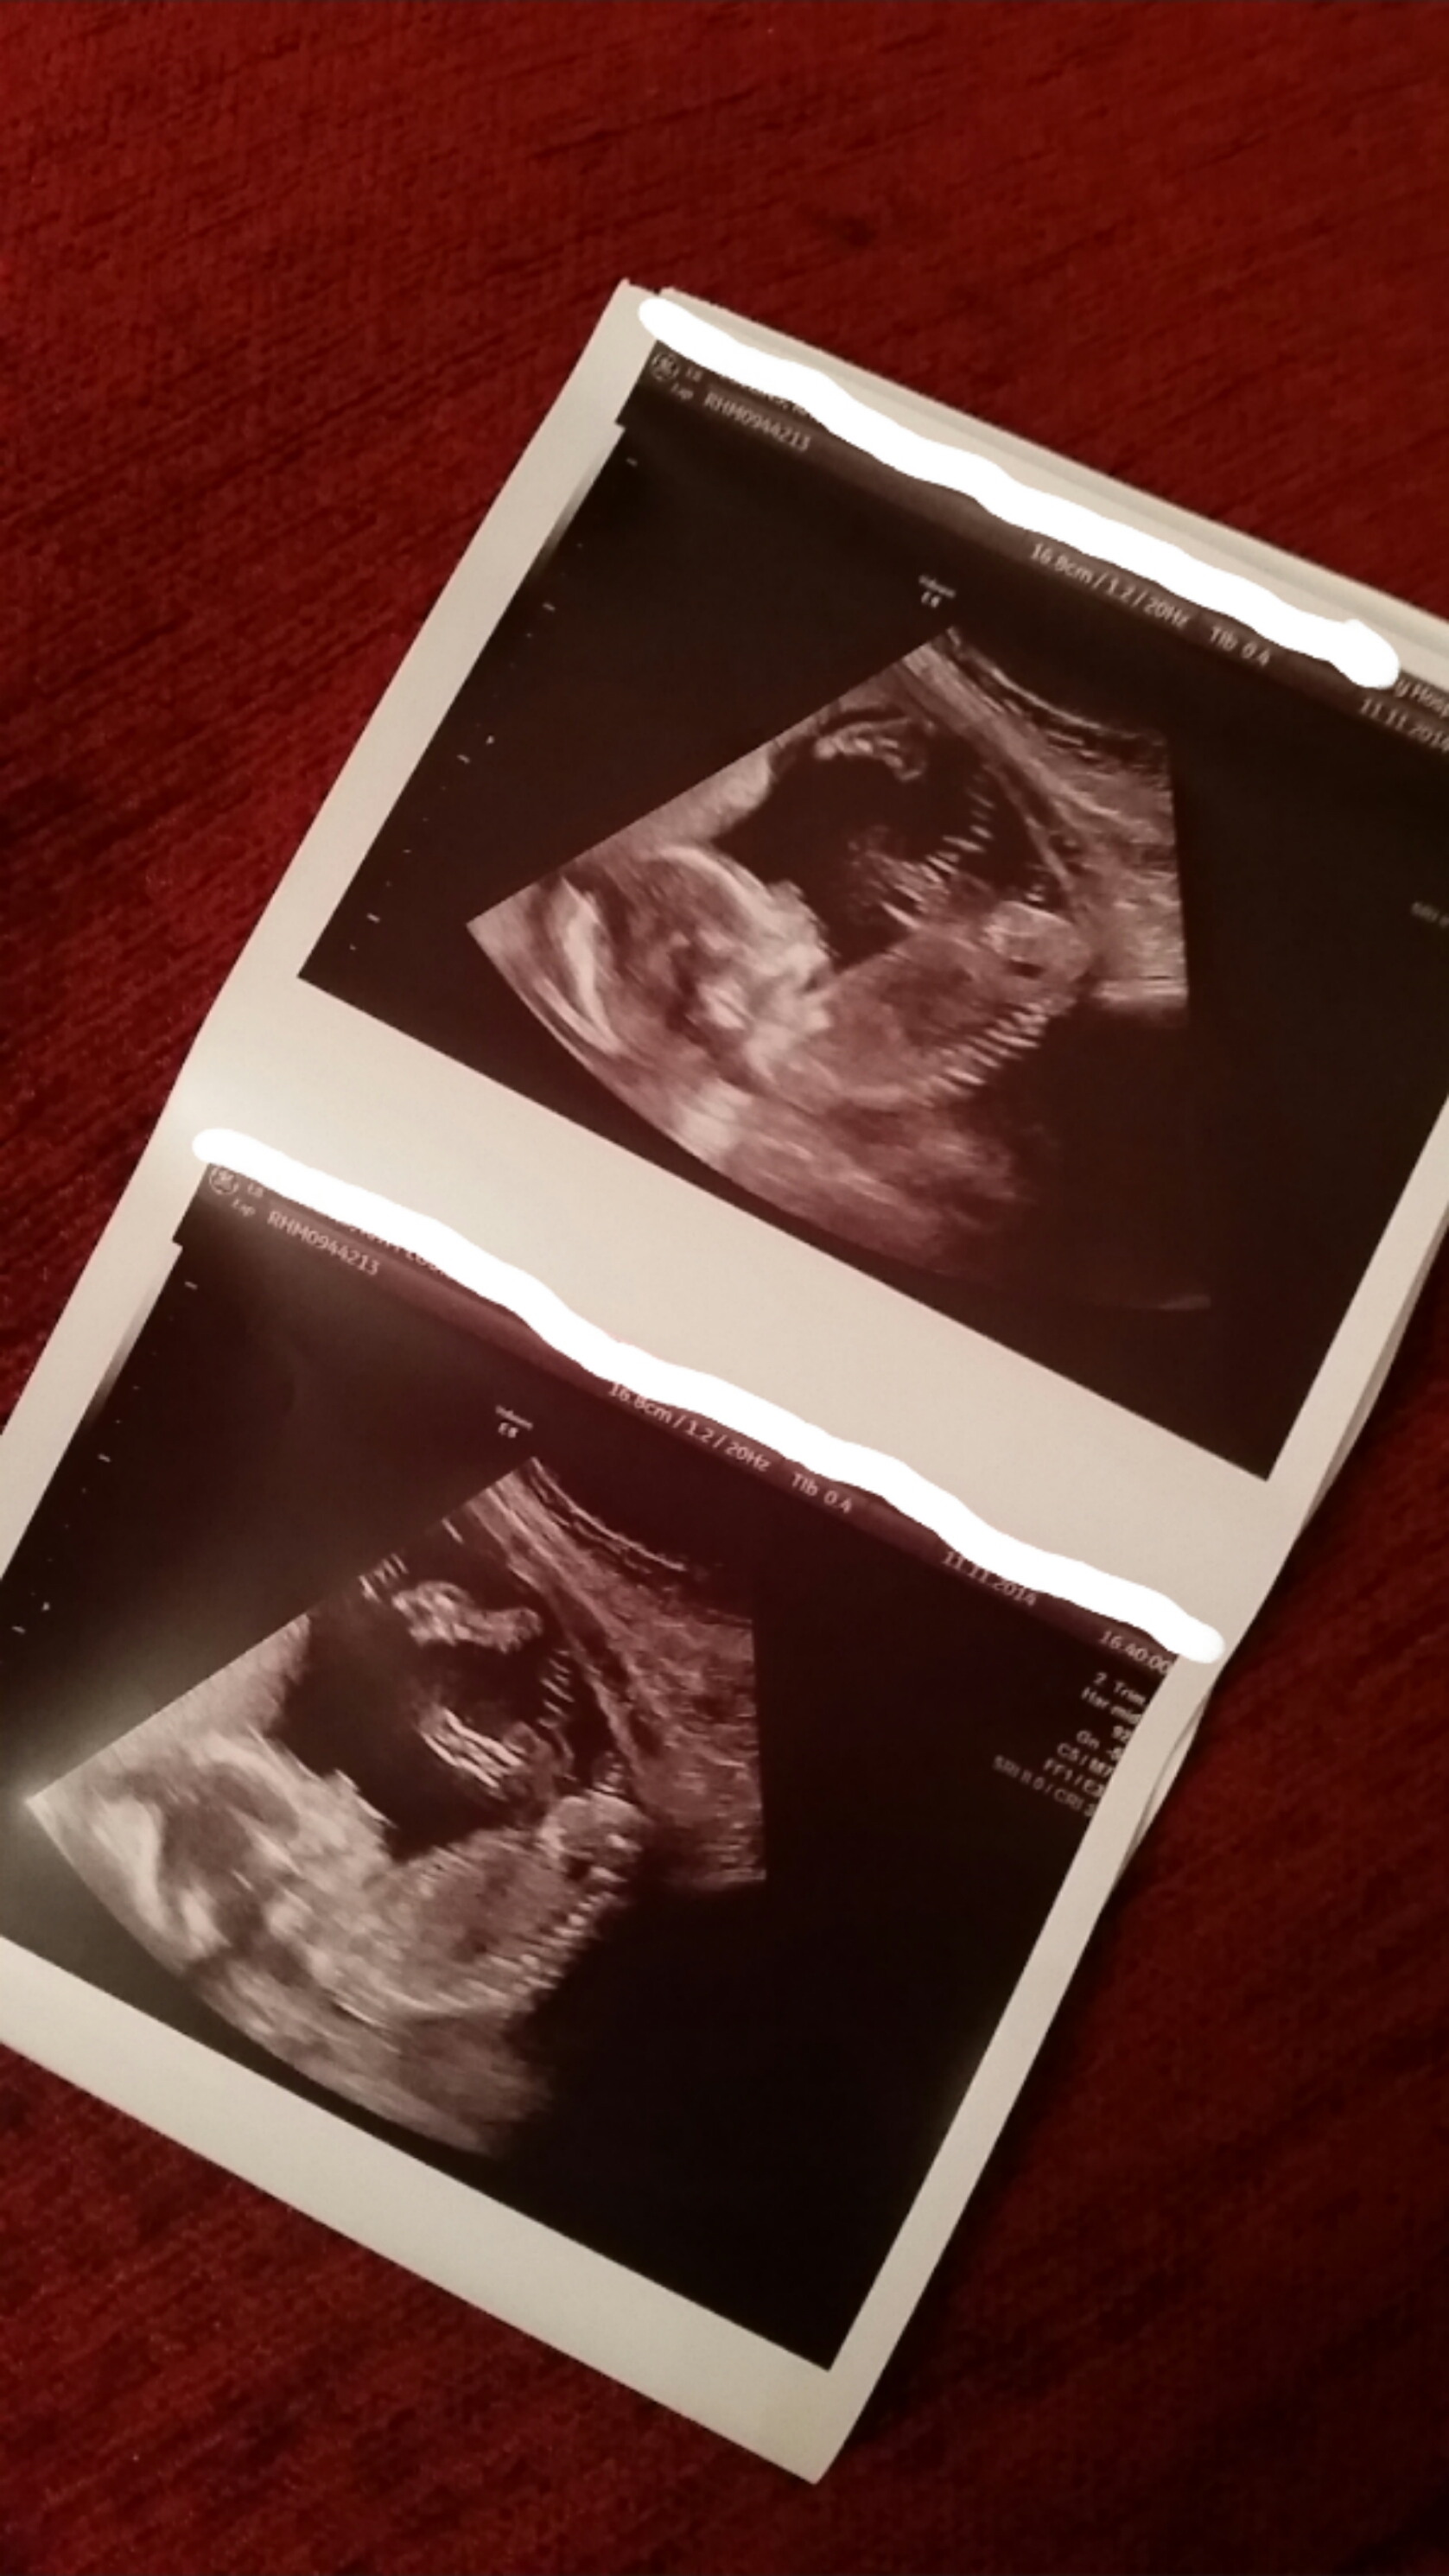

I don't know gender but thinking looks girly from 20 week scan? Any thoughts?

I'm not seeing any obvious 'snail' shape down there which would show little boy parts but I just can't get the detail good enough to be sure I'm afraid:) Any chance of getting the second picture down (bottom picture of the 1st double picture:)) really close up for us and in as much detail as possible??

I think you need a potty shot. I can't see any gender clues in these pics.

I've seen a similar pic on another forum. They too were told girl but it's an odd shot to tell really.